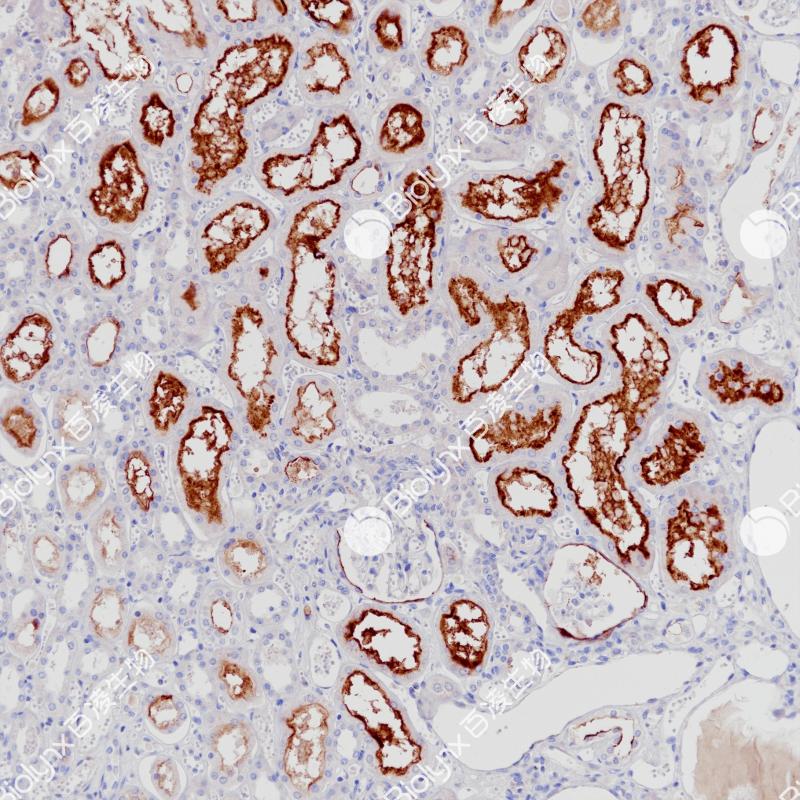

雌激素受体(ER)属于核受体超家族的类固醇受体,由553个氨基酸组成。雌激素受体分子具有三个结构域,即DNA结合中央结构域,C末端的激素结合结构域和N末端的转录激活结构域。ER参与女性性激素的调节功能,主要是17(E2),在一些目标组织的生长、分化和功能方面,如女性和男性生殖道,乳腺,骨骼和心血管系统。ER α存在于正常乳腺和子宫内膜组织的上皮细胞的细胞核,以及乳腺癌的亚型中。其次, ER α可作为一个肿瘤标志物,与抗孕酮受体的抗体组合,可用于腺癌的分类。

阳性对照

乳腺癌

亚细胞定位

细胞核